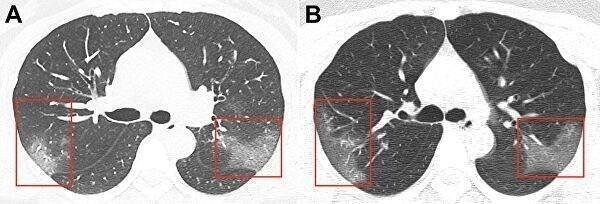

У переболевших COVID-19 без симптомов обнаружены поражения легких, сообщили японские ученые, изучавшие результаты компьютерной томографии заразившихся коронавирусом пассажиров лайнера Diamond Princess.

Результаты исследования опубликовал портал Радиологического общества Северной Америки. Из 104 человек, подхвативших инфекцию на корабле, у 76 болезнь протекала без симптомов. Однако у большинства "бессимптомных" пациентов (41 человек) в легких нашли изменения — "эффект матового стекла".

Исходя из этих данных, японские ученые пришли к выводу, что и при бессимптомном течении болезни легким наносится вред.